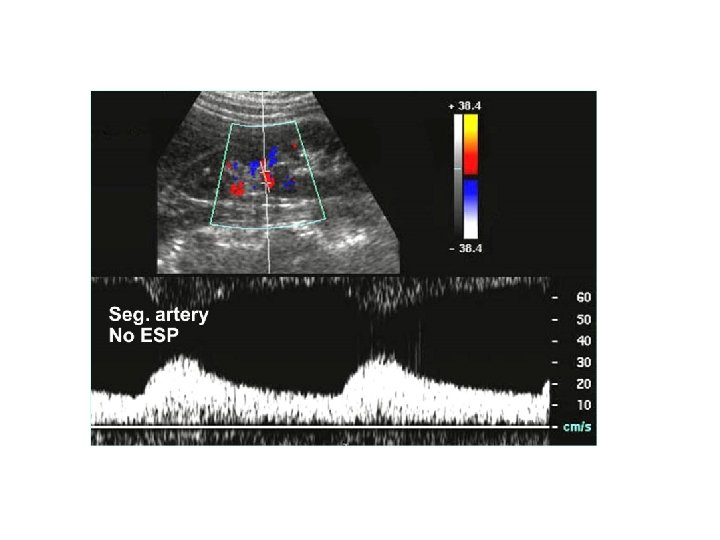

Peripheral Resistance Low resistance flow: Flow of a continuous (steady) nature feeding a dilated vascular bed. lots of flow in Diastole Going to organs

High resistance flow: Flow of a pulsatile nature. Between incident pulses, hydraulic reflections travel back up the vessel from the periphery producing flow reversals in the vascular compartment. Example arteries: ECA, subclavian, aorta, iliac, extremity arteries, fasting SMA

The reversal component of a high resistant signal may disappear distal to a stenosis because of decreased peripheral resistance, secondary to ischemia. Doppler flow distal to a significant stenosis is lower resistance. In addition, it is more rounded in appearance and is weaker in strength.

A normally high resistant (biphasic or triphasic) signal may become monophasic as it approaches the significant stenosis and or arterial obstruction. Doppler flow proximal to a significant stenosis is higher resistant in quality (could have no diastole or minimal diastole).